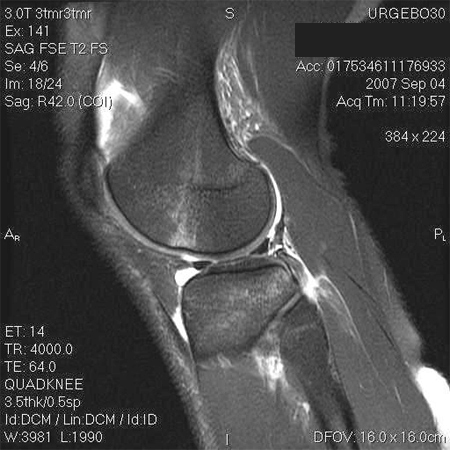

RNM ponderada em T2 mostrando fratura por impactação do côndilo femoral do compartimento lateral e do platô tibial, derrame e achatamento do sulco terminal que ocorre com a manobra do ressalto (pivot shift) em lesão do LCA.

Do acervo pessoal de Philip H. Cohen